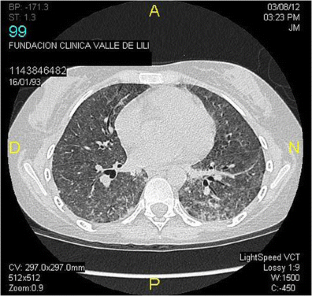

Fig. 1